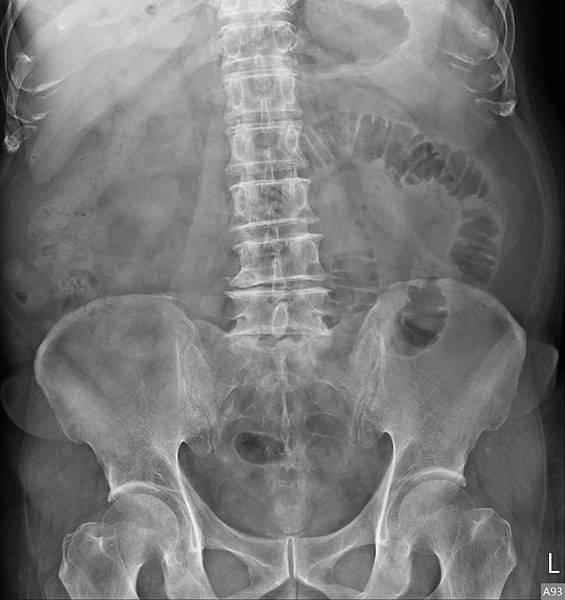

下面的病人,80歲女性,長期胃食道逆流,每半年做一次胃鏡(診斷GERD LA Gr A),斷斷續續吃PPI兩三年。GERD LA Gr A這種診斷是假的胃食道逆流,方便醫師開PPI而已。照一張X光片,真實的情況如下:

她的問題出在腸道產氣細菌製造出來的腸氣影響(抑制)大腸蠕動,大腸蠕動慢,吸收水分多,造成升結腸的糞便因水分吸收過多而呈羊屎狀。解決方式是「清腸+益生菌」,兩週後的X光片如下: